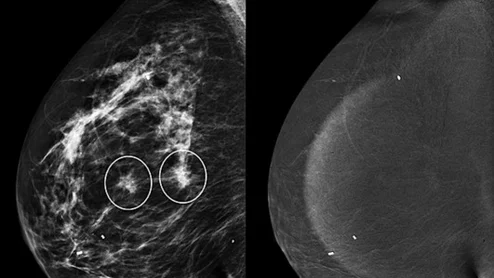

Non-enhancing asymmetries on contrast-enhanced mammography

Patients with asymmetries on CEM typically are recalled for additional views, ultrasound and occasionally MRI. But the extra workup might not be necessary.